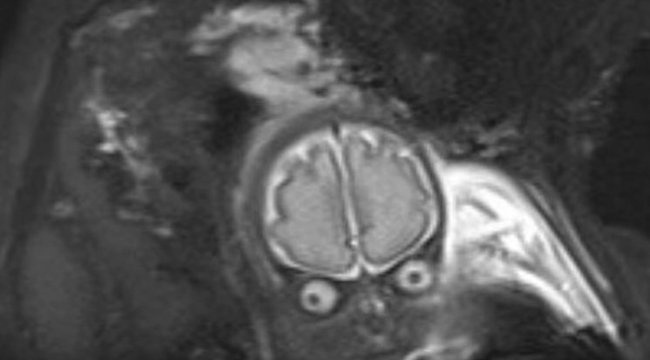

Az angliai Bury-ben élő fiatal pár, Laura Thomas és Matthew Tansley majdnem sokkot kaptak, amikor a nőgyógyásznál meglátták a 30 hetes magzatukat egy ultrahangfelvételen.

A pici ugyani valami egészen elképesztő arcát mutatta, ami szülei szerint – nagyon találóan – leginkább Tim Burton klasszikus filmjének, a Támad a Mars! egyik űrlényére emlékeztet.

Szerencsére a babának valóban nem volt semmi baja, teljesen egészségesen, – és talán, ami a szüleinek a legfontosabb – emberi lényként jött a világra. Most pedig, hogy minden rendben van a kis Lucas-szal, – aki szülei elmondása szerint egy boldog, gyönyörű kisfiú, aki mindenkit azonnal levesz a lábáról – úgy gondolták, másokat is megnevettetnek a felvétellel, ami mára már nekik is csak egy vicces emlék lett.